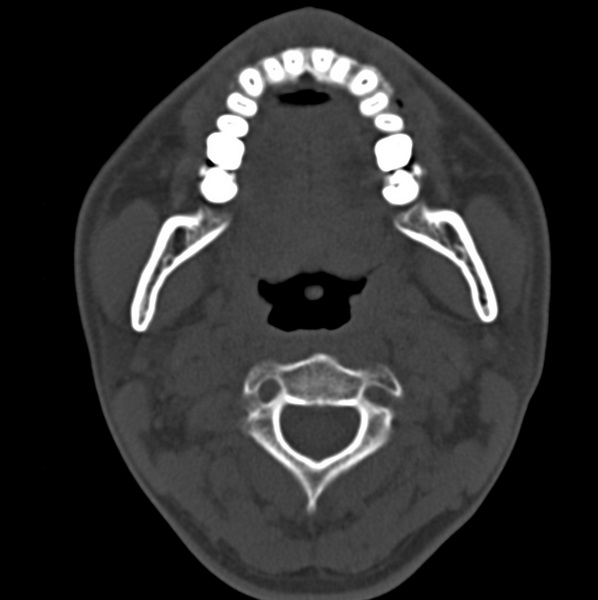

男、31、鼻咽部肿瘤放疗后请帮忙看看。

效果好,右侧破裂孔扩大,局部骨质缺损,为颅底骨质破坏。

1)鼻咽部肿瘤侵犯颅底放疗术后改变。2)左侧蝶窦炎。

咽后壁增厚,左侧咽鼓管隆突增大、咽鼓管咽口变浅,同侧咽旁间隙较窄。右侧颅底骨质破坏?为什么不在同一侧?

鼻咽部肿瘤侵犯颅底放疗术后改变.